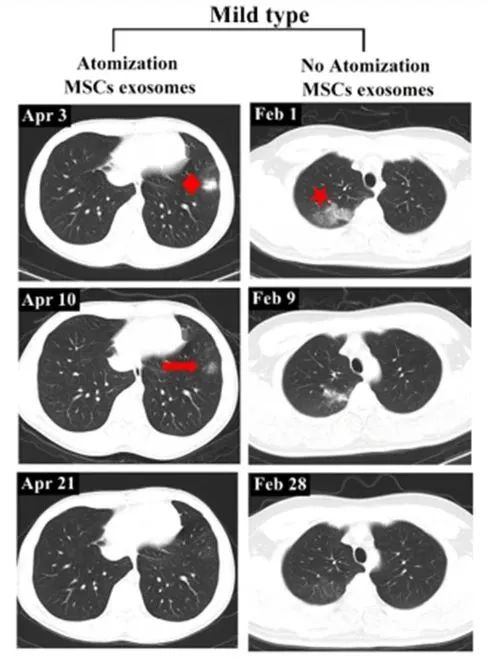

輕度病例前后影像變化:以患者 6 為例,2020 年 4 月 3 日,該患者第一次 CT 掃描顯示左肺下葉外有孤立結節,4 月 4 日,患者接受外泌體霧化治療,4 月 10 日,第二次 CT 檢查顯示左肺下葉結節密度明顯降低,大小也縮小,4 月 21 日,第三次 CT 檢查,左下肺病灶完全吸收,從發現結節到完全吸收肺部病變所需的時間為 18 天。

相比之下,另一例患者(輕度病例,無霧化治療)類似肺部病變的吸收時間為 27 天。

左:患者 6;右:無外泌體霧化治療的輕度病例